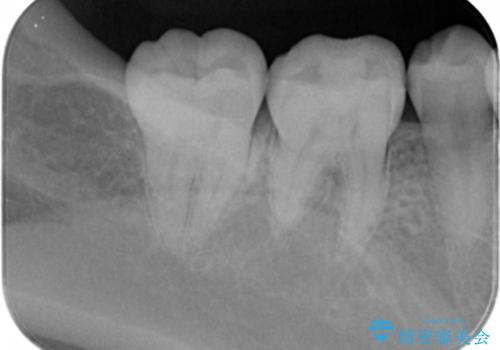

- 口を開けたとき銀歯が見えるのが嫌で白くしたいとの事で来院。

銀歯を除去してセラミックインレー(e-maxインレー)での治療となりました。